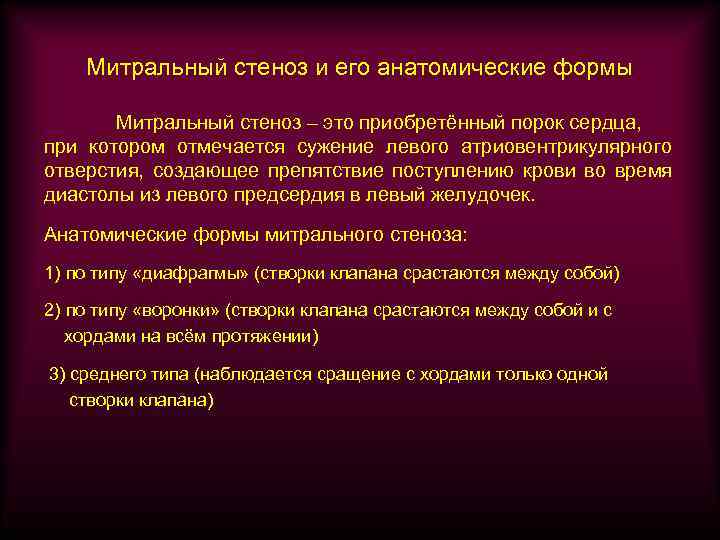

Фотографии и информация о приобретенных пороках сердца

Раздел: Фотосинтез идей